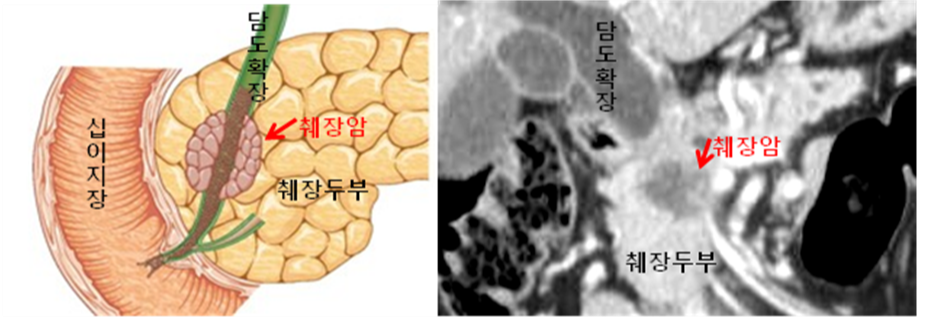

췌장암은 췌장 세포에서 시작되는 암입니다. 췌장은 소화액을 분비하고 인슐린과 같은 중요한 호르몬을 생성하는 기관으로, 상복부 뒤쪽에 위치하고 있습니다. 췌장암은 발견이 늦어지는 경우가 많아 '침묵의 암'으로도 불립니다.

췌장암은 일반적으로 췌장의 외분비 부분에서 발생하며, 이를 '췌장 선암'이라고 합니다. 췌장암의 다른 유형으로는 신경내분비 종양이 있지만, 이는 상대적으로 드문 형태입니다.

췌장암의 진단 방법

췌장암 진단을 위해 의사들은 다양한 검사와 영상 기법을 사용합니다:

- 영상 검사: CT 스캔, MRI, 내시경 초음파(EUS)